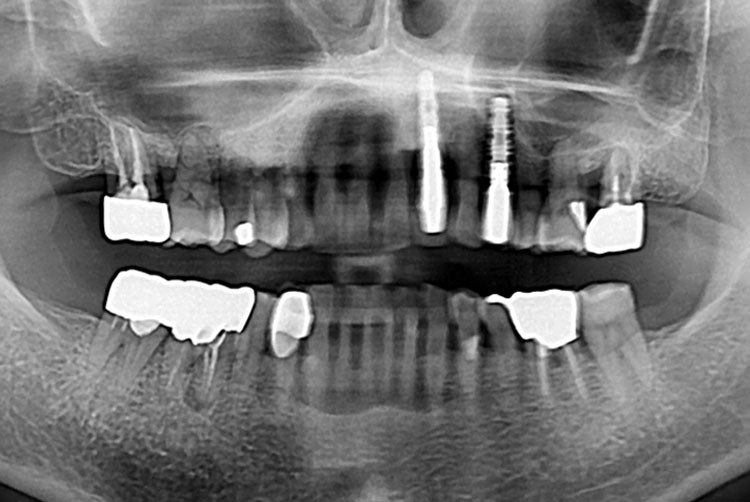

[임플란트] 임플란트

치료전 : 2018-07-21

세종치과는 많은 환자와 다양한 케이스를 바탕으로 항상 편안한 임플란트 수술을 제공하고자 노력하고,

오래동안 튼튼히 쓸 수 있는 임플란트 수술을 가장 큰 목표로 삼고 있습니다.